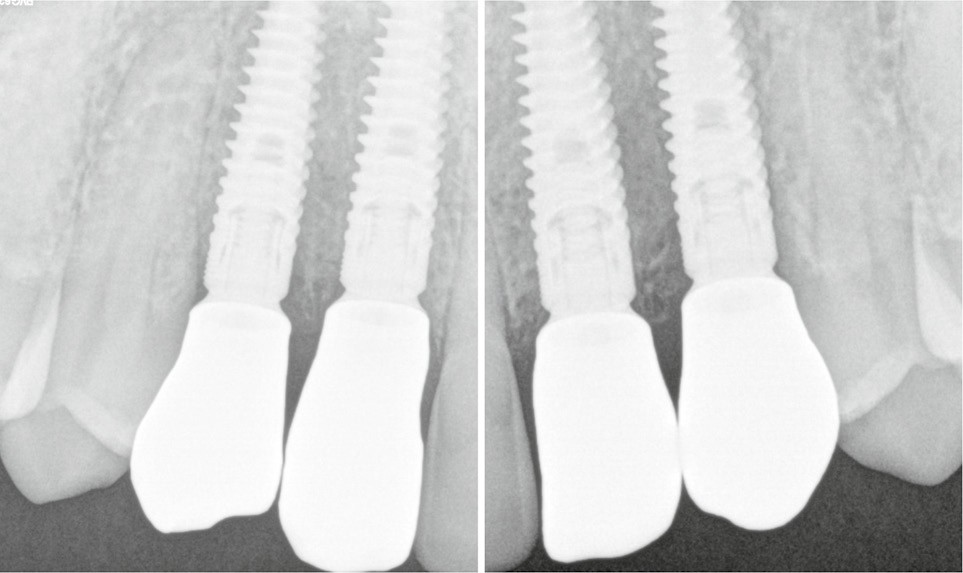

- pose des couronnes d’usage selon le protocole classique (fig. 9 et 10a) ;

- radiographies de contrôle (fig. 10b).